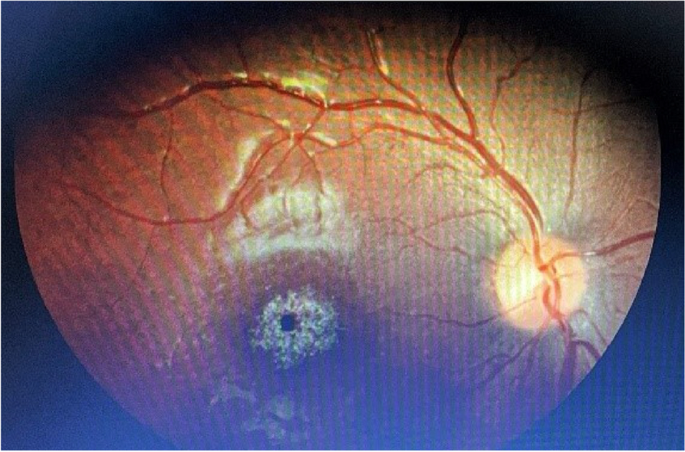

As Bardet-Biedl Syndrome (BBS) is slowly gaining recognition, most of the diagnostic companies are also entering the market for the development of BBS diagnostic kits. Bardet-Biedl Syndrome is the rare occurrence of retinal dystrophy, obesity, polydactyly, and renal defect occurring in an autosomal recessive manner. To manage the syndrome in time, the correct diagnosis is essential. The market is expanding steadily as DNA sequencing technologies and next-generation sequencing (NGS), bioinformatics tools offer accurate detection of the mutations in several genes that cause BBS. The accuracy and affordability of diagnostic tests will improve as healthcare institutions, genetic research centres, and biotech companies collaborate more.